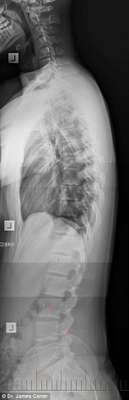

As imagens de raio-x abaixo mostram os malefícios do uso excessivo de smartphones e tablets para o corpo de adolescentes e crianças. Espinhas dorsais completamente curvadas que resultam em problemas graves de coluna e para o pescoço é a principal consequência da tecnologia para a saúde da nova geração.

17 anos, 16 anos e 7 anos

17 anos, 16 anos e 7 anos - Dr. James Carter